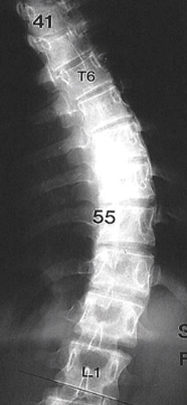

수술적 치료

만곡이 40도 이상인 경우에는 척추고정술을 통해 수술적인 치료를 시행합니다.

교정전

교정후